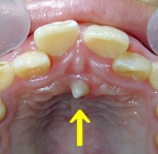

⭐ 実際のケース:息子の過剰歯に気づいた瞬間

私の次男にも過剰歯がありました!

歯磨き中、前歯の乳歯が異常にグラグラしていることに気づき、

「ぶつけた?」と聞いても本人は心当たりはなし。

院長にレントゲン撮影してもらうと、

しっかりと過剰歯が写っていました。

その後すぐに乳歯が抜け、尖った過剰歯が顔を出してきました。

さらに、次男は2本の過剰歯があり、

もう1本は奥に埋まっていて、通常とは逆方向に生えている

逆性過剰歯(ぎゃくせいかじょうし)でした。